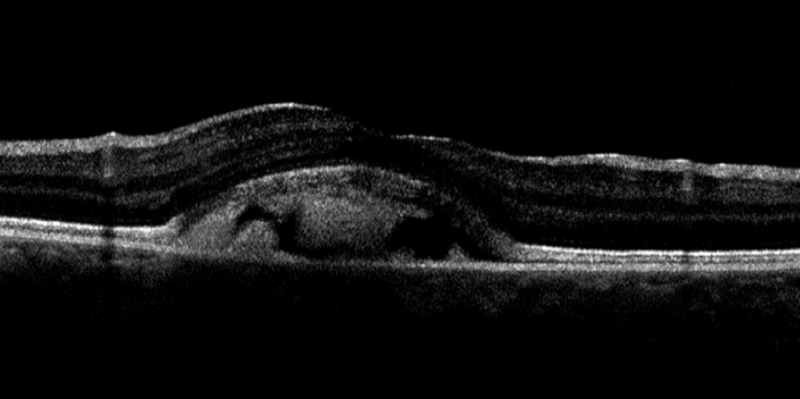

También obtuvimos imágenes de tomografía de coherencia óptica de madre e hija:

Figura 3a.

Figura 3b.

Figura 4a

Figura 4b.

¿Qué hallazgos tomográficos se pueden describir?

Respuesta correcta: e

En la imagen de OCT de la hija (Figura 3a y Figura 3b) vemos una imagen hiperreflectiva por encima del EPR, más heterogénea en OD (estadio viteloruptivo) y fijándonos en la línea ESI ésta está integra en ambos ojos, no es el caso de la madre (Figura 4b) donde vemos una discontinuidad. La imagen de OCT del ojo derecho (Figura 4a) de la madre no muestra hallazgos patológicos.